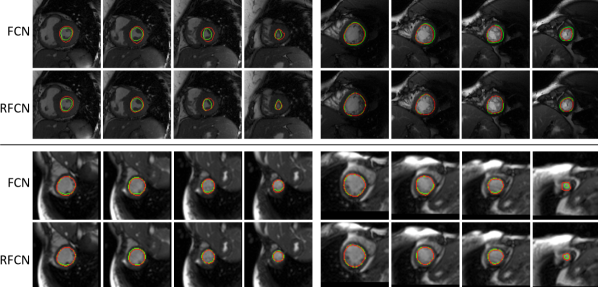

This section presents an empirical evaluation of several LV endocardium segmentation algorithms using three performance metrics: good contours (GC) [1], Dice index, and average perpendicular distance (APD) between manually drawn and predicted contours [21]. In order to make our experimental results comparable with published studies on MICCAI dataset, all models were validated using the online set, and we report on results obtained on the validation set. Table 1 summarises the experimental results. On the MICCAI dataset, the DBN-based results presented in [17] include a Dice index of , a GC of and an APD of mm whereas the pipeline described in [1] results in a Dice index of , a GC of and an APD of mm (before further post-processing). A comparable Dice index is obtained by both FCN and RFCN, which yield higher GC and smaller ADP. Here RFCN outperforms FCN with a substantially improved ADP of mm.

In order to shed insights into the regional improvements introduced by RFCN, the Dice index was computed separately for different local regions of the LV, and the results are summarised in Table 2. Here, Base-, Base- and Base- indicates that , and slices were taken starting from the base of the heart and moving towards the middle, and analogously for the apex. All the remaining slices contributed towards the Central class. In all cases, the Dice index is calculated using all the samples at once to reflect overall pixels accuracy. In both datasets, RFCN outperforms FCN around the central slices and around the apex, as expected. However, in the MICCAI dataset, FCN yields better performance around the base of the heart. On the PRETERM dataset, both DBN and RDBN gave the worst performance, compared to FCN and RFCN, despite using focused region of interests instead of full-sized images. Here again it can be observed that RDBN improves upon DBN across all cardiac locations.